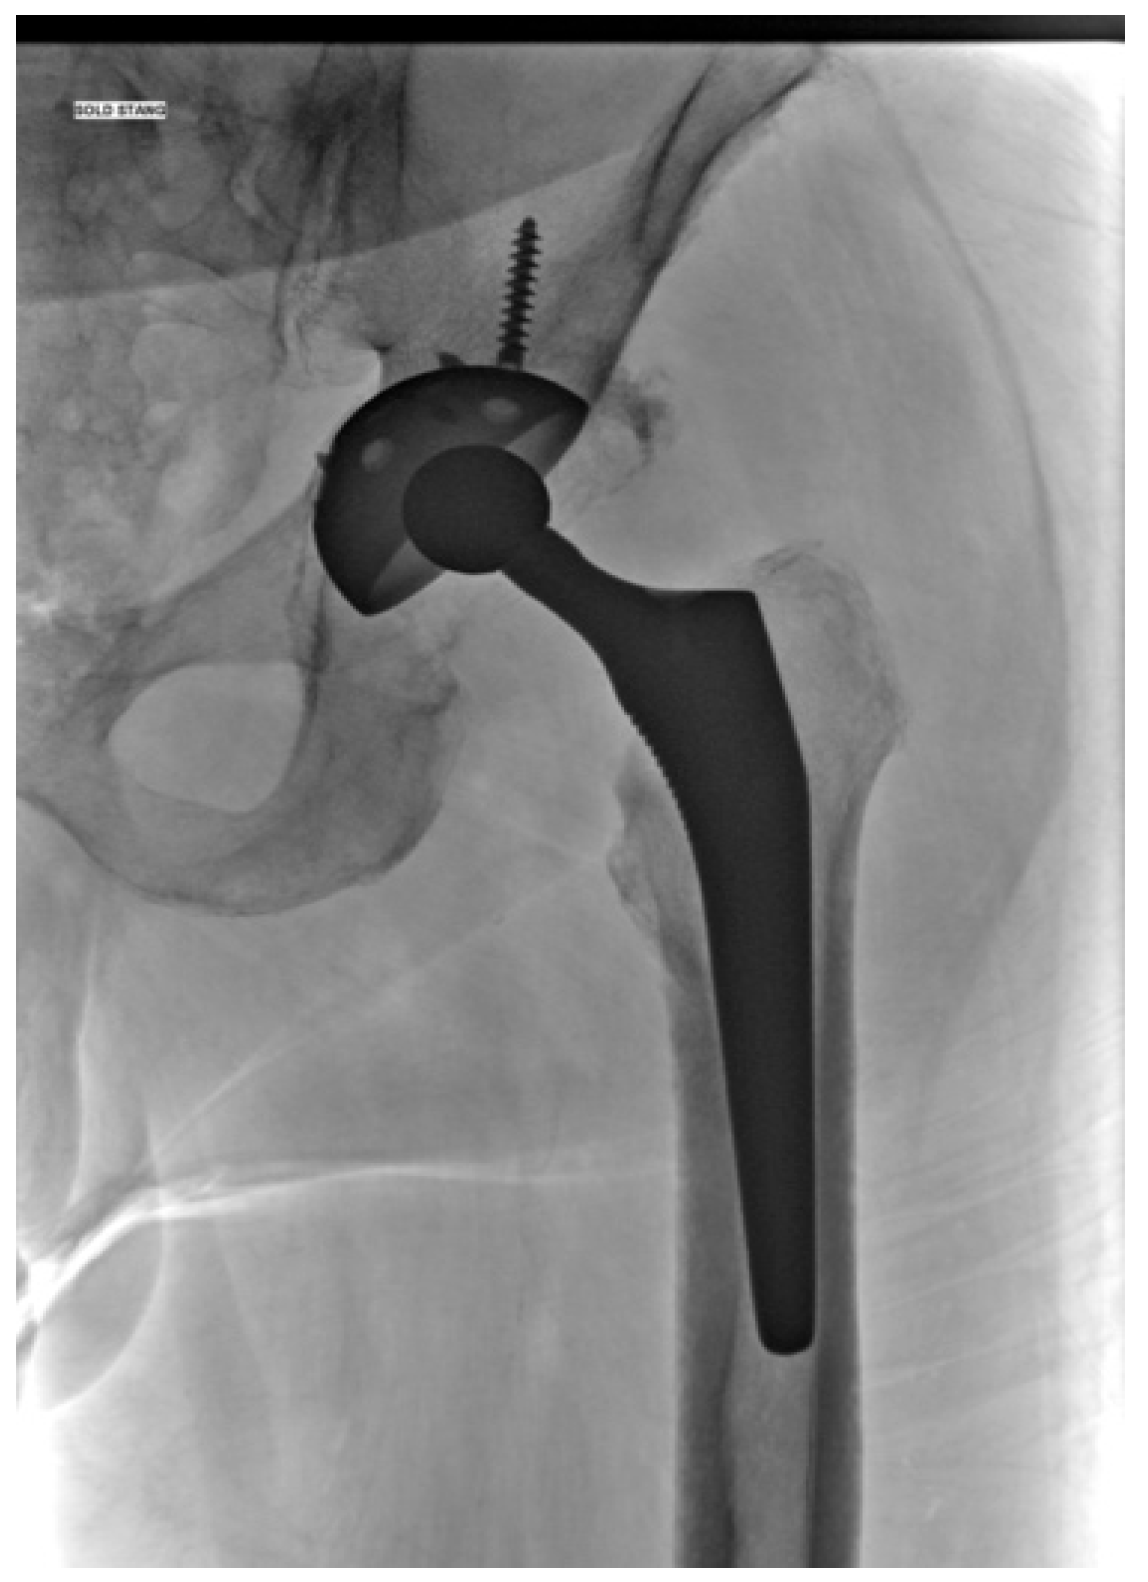

The Efficacy of Antibiotic-Loaded Calcium Sulfate Beads (Stimulan) in Patients with Hip Arthroplasty Infections

2.4. Surgical Procedure